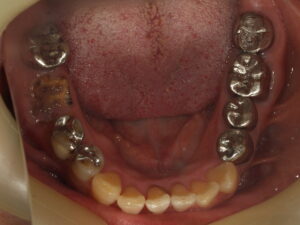

この2つの写真を見比べて、どちらのお口の中の印象が良く見えますか?(比較写真2枚)

術前

この患者さまはお口を開けた時に銀歯が目立つということで、順番に白い被せ物に変えていきました。